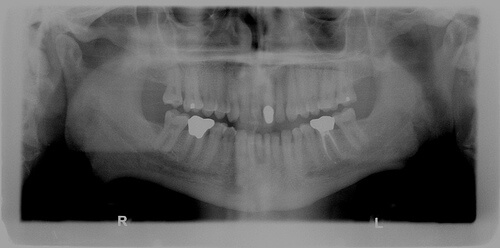

Dental X-rays are a useful diagnostic tool when helping your dentist detect damage and disease not visible during a regular dental exam. How often X-rays should be taken depends on your present oral health, your age, your risk for disease, and any signs and symptoms of oral disease. For example, children may require X-rays more often than adults because their teeth and jaws are still developing and their teeth are more likely to be affected by tooth decay than those of adults.

If you are a new patient, the dentist may recommend X-rays to determine the present status of your oral health and have a baseline to help identify changes that may occur later. A new set of X-rays may be needed to help your dentist detect any new cavities, determine the status of your gum health or evaluate the growth and development of your teeth. If a previous dentist has any radiographs of you, your new dentist may ask you for copies of them. Ask both dentists to help you with forwarding your X-rays.